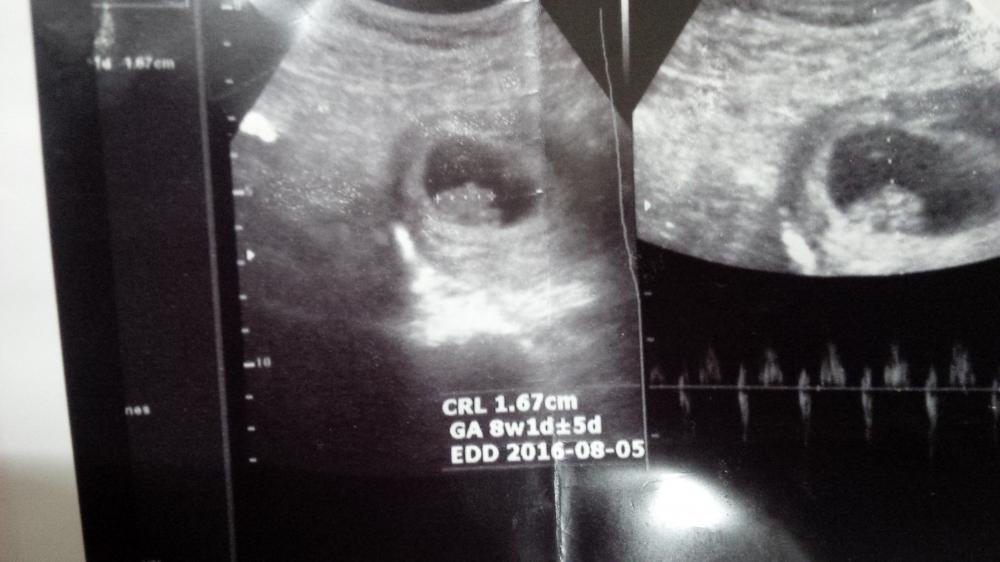

اخت رنا انا بنزل صورة الجنين وياريت تقولي ايش هوه

اعتقد بنوته والعلم عند الله وحده

كم اسبوع

بس باين الصوره بعمر 10 اسابيع او 9 اسابيع

المهم احساي يقول انها بنوته